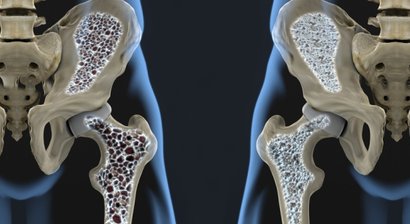

Hüftgelenksnahe Frakturversorgung

Schenkelhalsfraktur Der Oberschenkelhalsbruch, auch Schenkelhalsfraktur genannt, zählt zu den am häufigsten auftretenden osteoporotischen Frakturen. Das Risiko für Schenkelhalsfrakturen steigt mit zunehmendem Alter. Ältere Menschen mit einer bestehenden Osteoporose sind deshalb b...